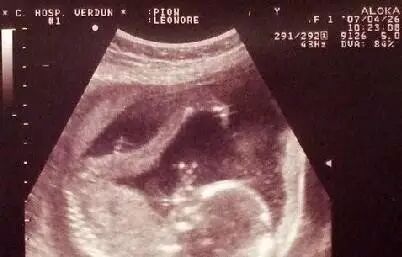

先天性马蹄内翻足的诊断大致可以分为两个阶段:I)产前诊断:最早可在妊娠 12-16 周即可通过三维或四维超声发现胎儿马蹄内翻足畸形的存在;II)出生后诊断:出生后通过临床检查可以明确诊断。